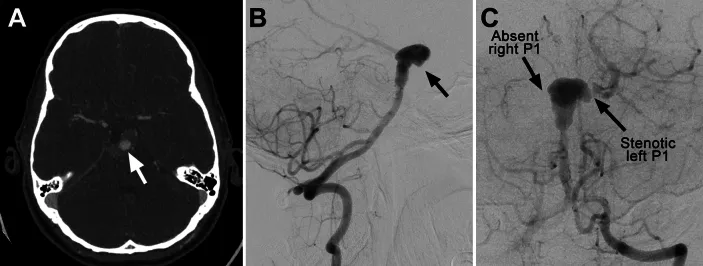

数字减影血管造影检查证实基底动脉顶端动脉瘤部分血栓形成,左侧大脑后动脉自动脉瘤发出。右侧大脑后动脉及双侧小脑上动脉未显影,血供来源于小脑前下动脉软脑膜侧支循环。左侧颈内动脉动脉瘤测量尺寸为16.9×25.9×20.5毫米。

数字减影血管造影影像显示:轴位CT血管造影可见部分血栓形成的巨大型基底动脉瘤;侧位投影显示基底动脉顶端动脉瘤部分血栓形成;前后位投影可见左侧大脑后动脉自动脉瘤发出,右侧P1段缺如,左侧P1段狭窄,双侧小脑上动脉未显影。